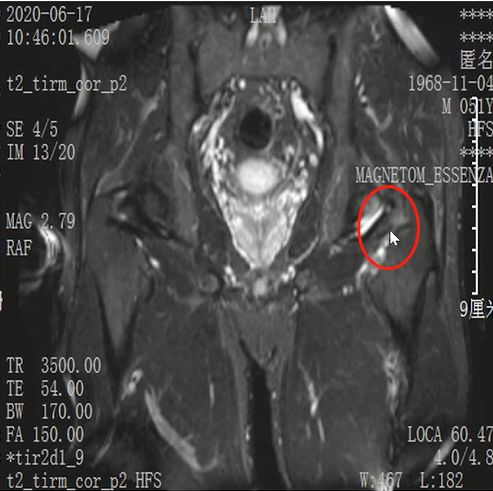

Lisfranc损伤在多发伤病人中常常容易漏诊,大约为 20-30%的漏诊率!